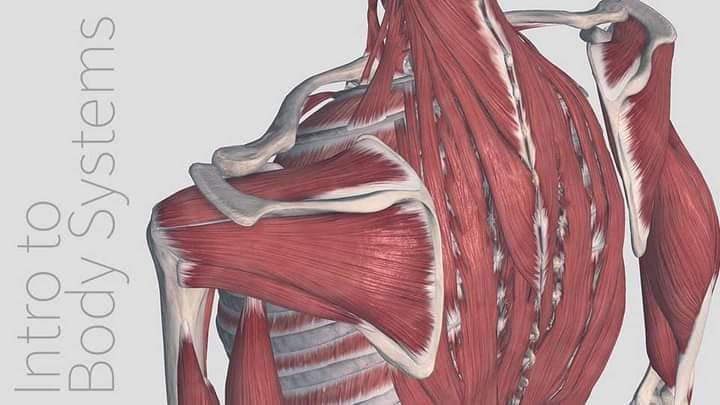

Спинні м'язи

Спинні м'язи виконують функції підтримки хребта, а також дозволяють здійснювати рухи тулуба.

Поверхневі спинні м'язи

М'язи, що піднімають лопатку: Трапецієподібний м'яз: великий м'яз, що покриває верхню частину спини. Його функція - підтримка і рух лопаток, а також забезпечення стабільності хребта.

М'язи, що ведуть лопатку до хребта: Широкий м'яз спини: великий м'яз, що розташований в нижній частині спини. Він відповідає за рухи плечей і лопаток, а також за розширення верхньої частини тулуба.

Глибинні спинні м'язи

М'язи, що забезпечують стабільність хребта: М'язи, що розташовані між хребцями: включають мускулатуру, яка забезпечує стабільність і підтримку хребта, а також дозволяє здійснювати рухи хребта.

М'язи, що здійснюють ротацію та нахили

М'язи, що забезпечують ротацію хребта: Ротаційні м'язи: допомагають у здійсненні обертальних рухів тулуба, а також у підтримці рівноваги і стабільності хребта.